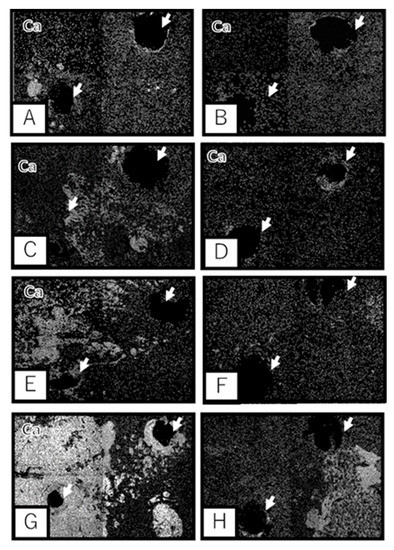

3.2. Scanning Electron Microscopic Observation

3.3. Histological Observation